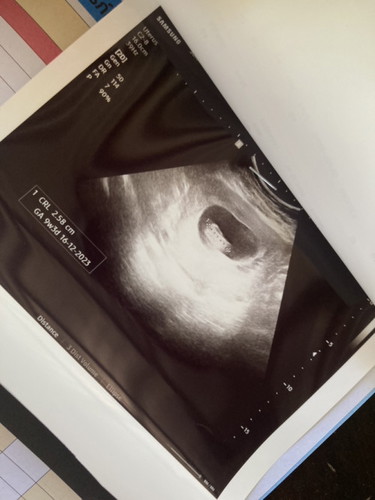

9วีค3วันแล้วนะคะ ภาพอัลตราซาวด์ครั้งแรก